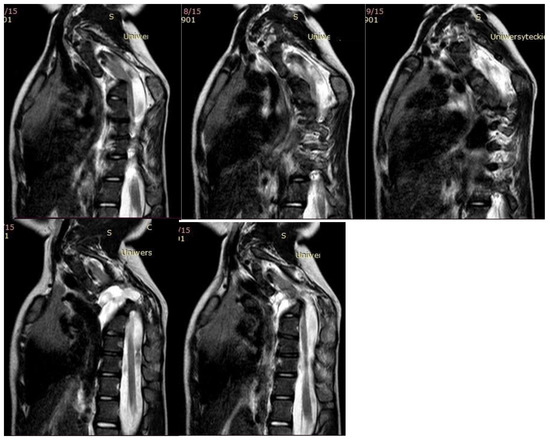

Neurological examination before the surgical treatment indicated neurological function was intact. MRI and CT performed before the surgery showed multilevel mixed congenital spinal anomalies in the cervical and thoracic spine, without spinal cord pathologies (hemivertebrae, blocked vertebrae, Figure 2 and Figure 3).

Figure 3. MRI of the five-year-old girl before surgical treatment.